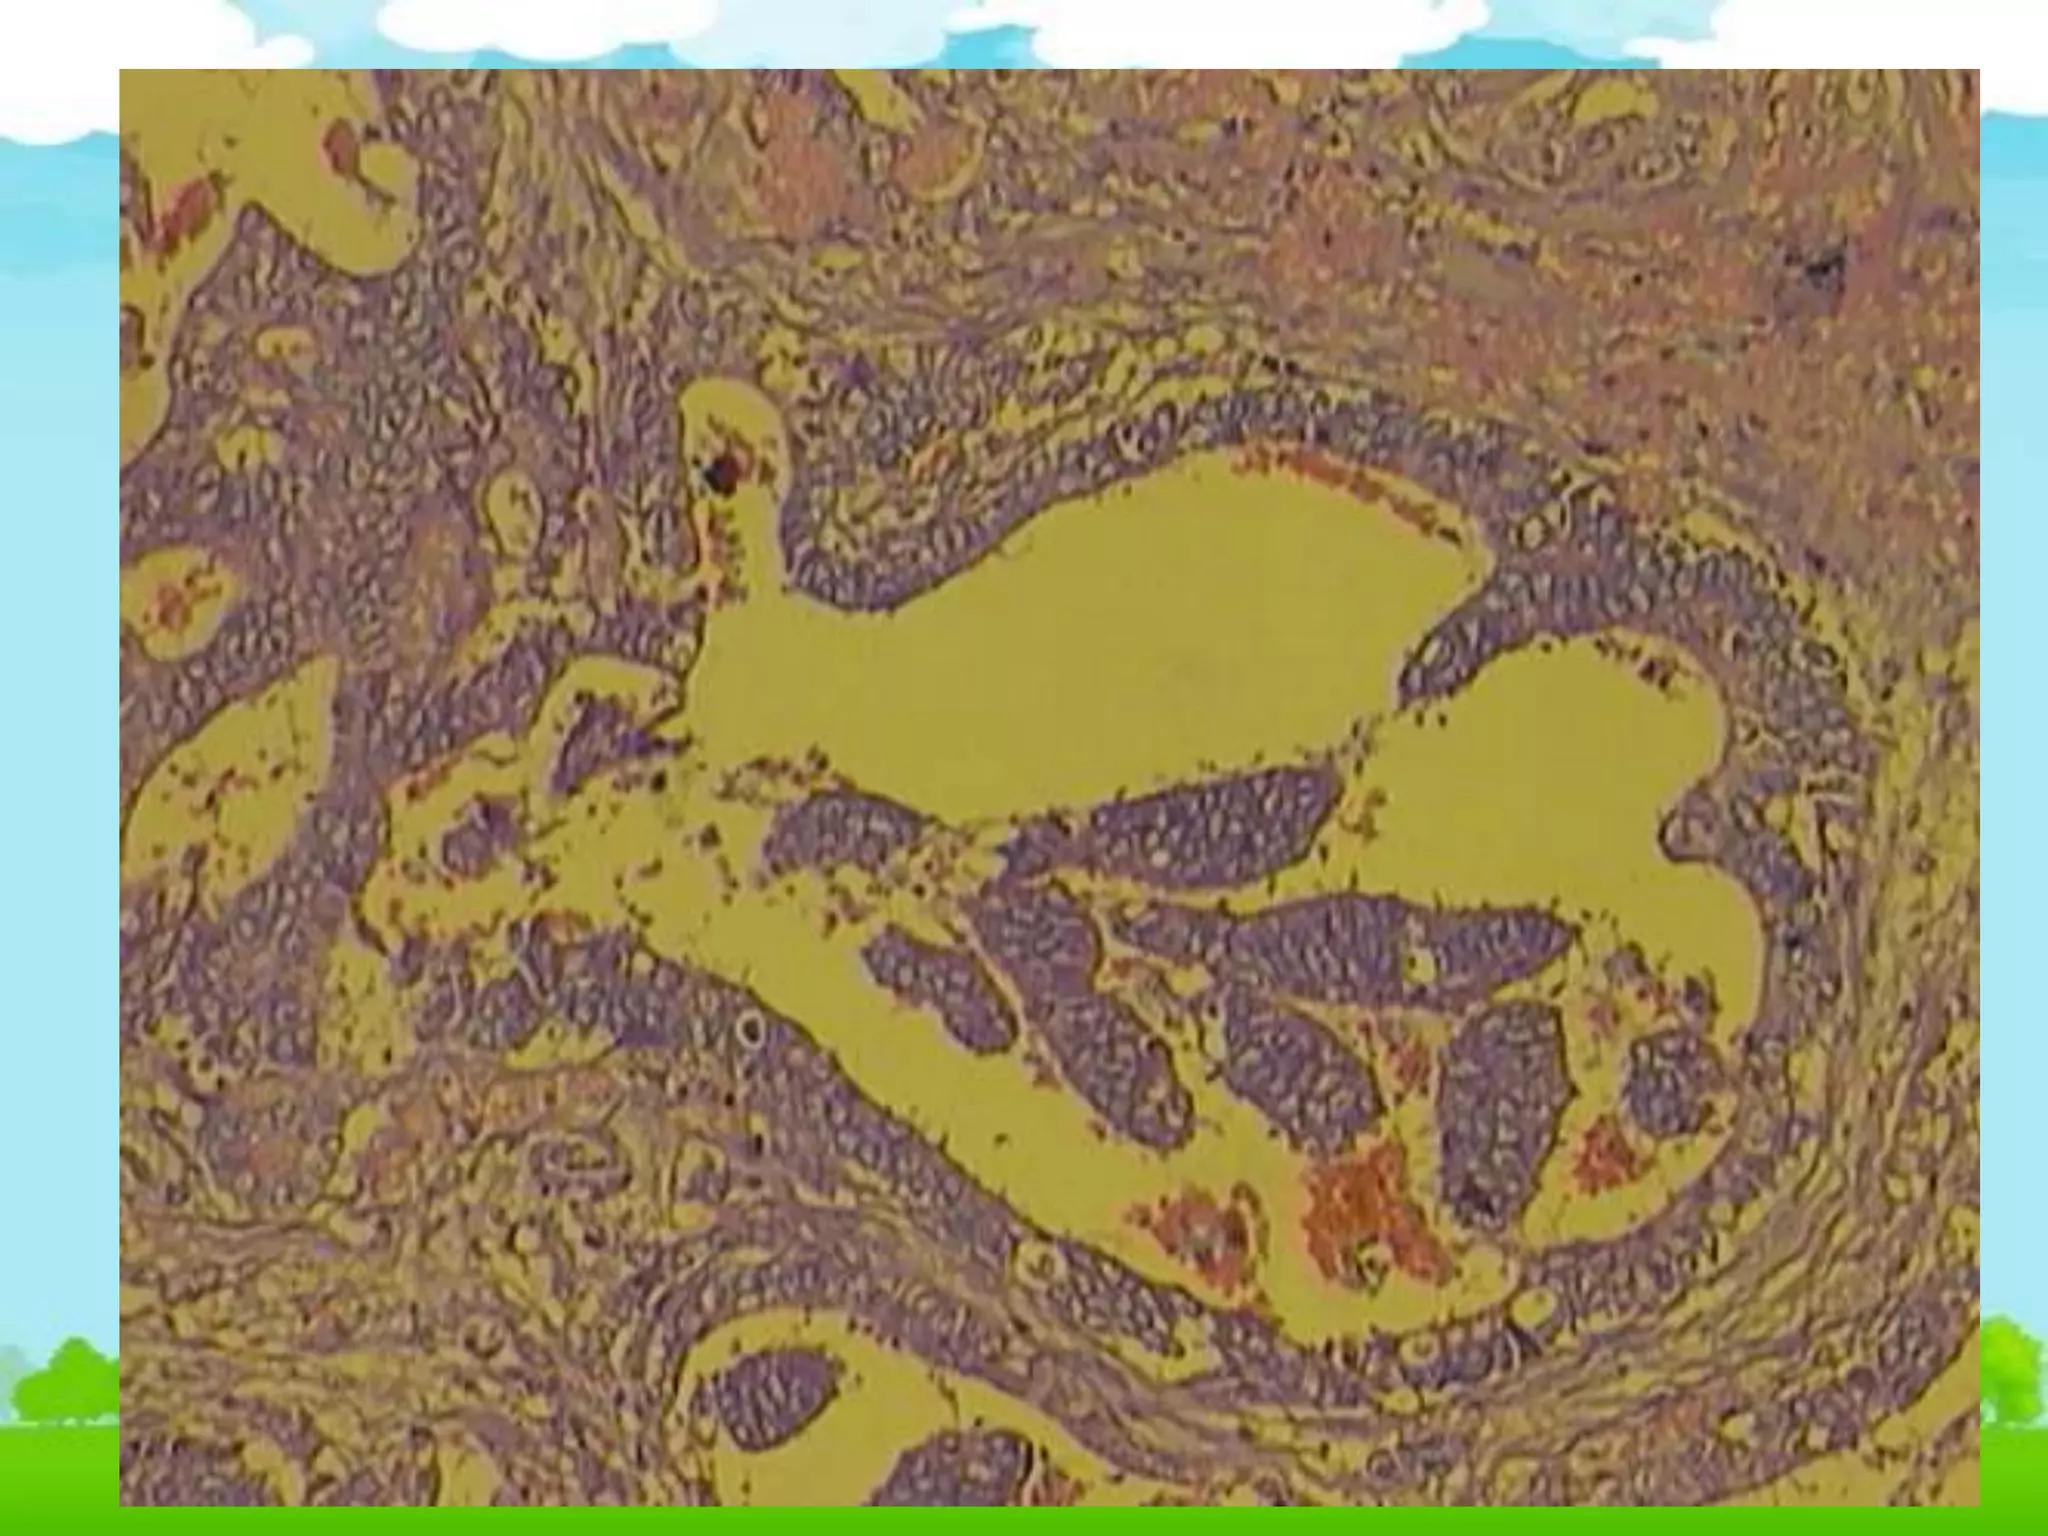

4. Carcinoma ống xâm nhập tuyến vú

• ĐN: là u ác tính phát sinh từ tế bào biểu mô ống

dẫn của tuyến vú, xếp thành ống, tuyến hoặc

thành bè, dải.

 Tế bào u: đa dạng hình thái (trụ, vuông, đa

diện...), to nhỏ không đều, hạt nhân rõ.

 Mô u: đa dạng: Ống nhỏ, tuyến, bè, dây dải,...,

xâm nhập mô lân cận (mô mỡ, cơ)

 Mô đệm: Tăng sinh xơ, viêm mạn.